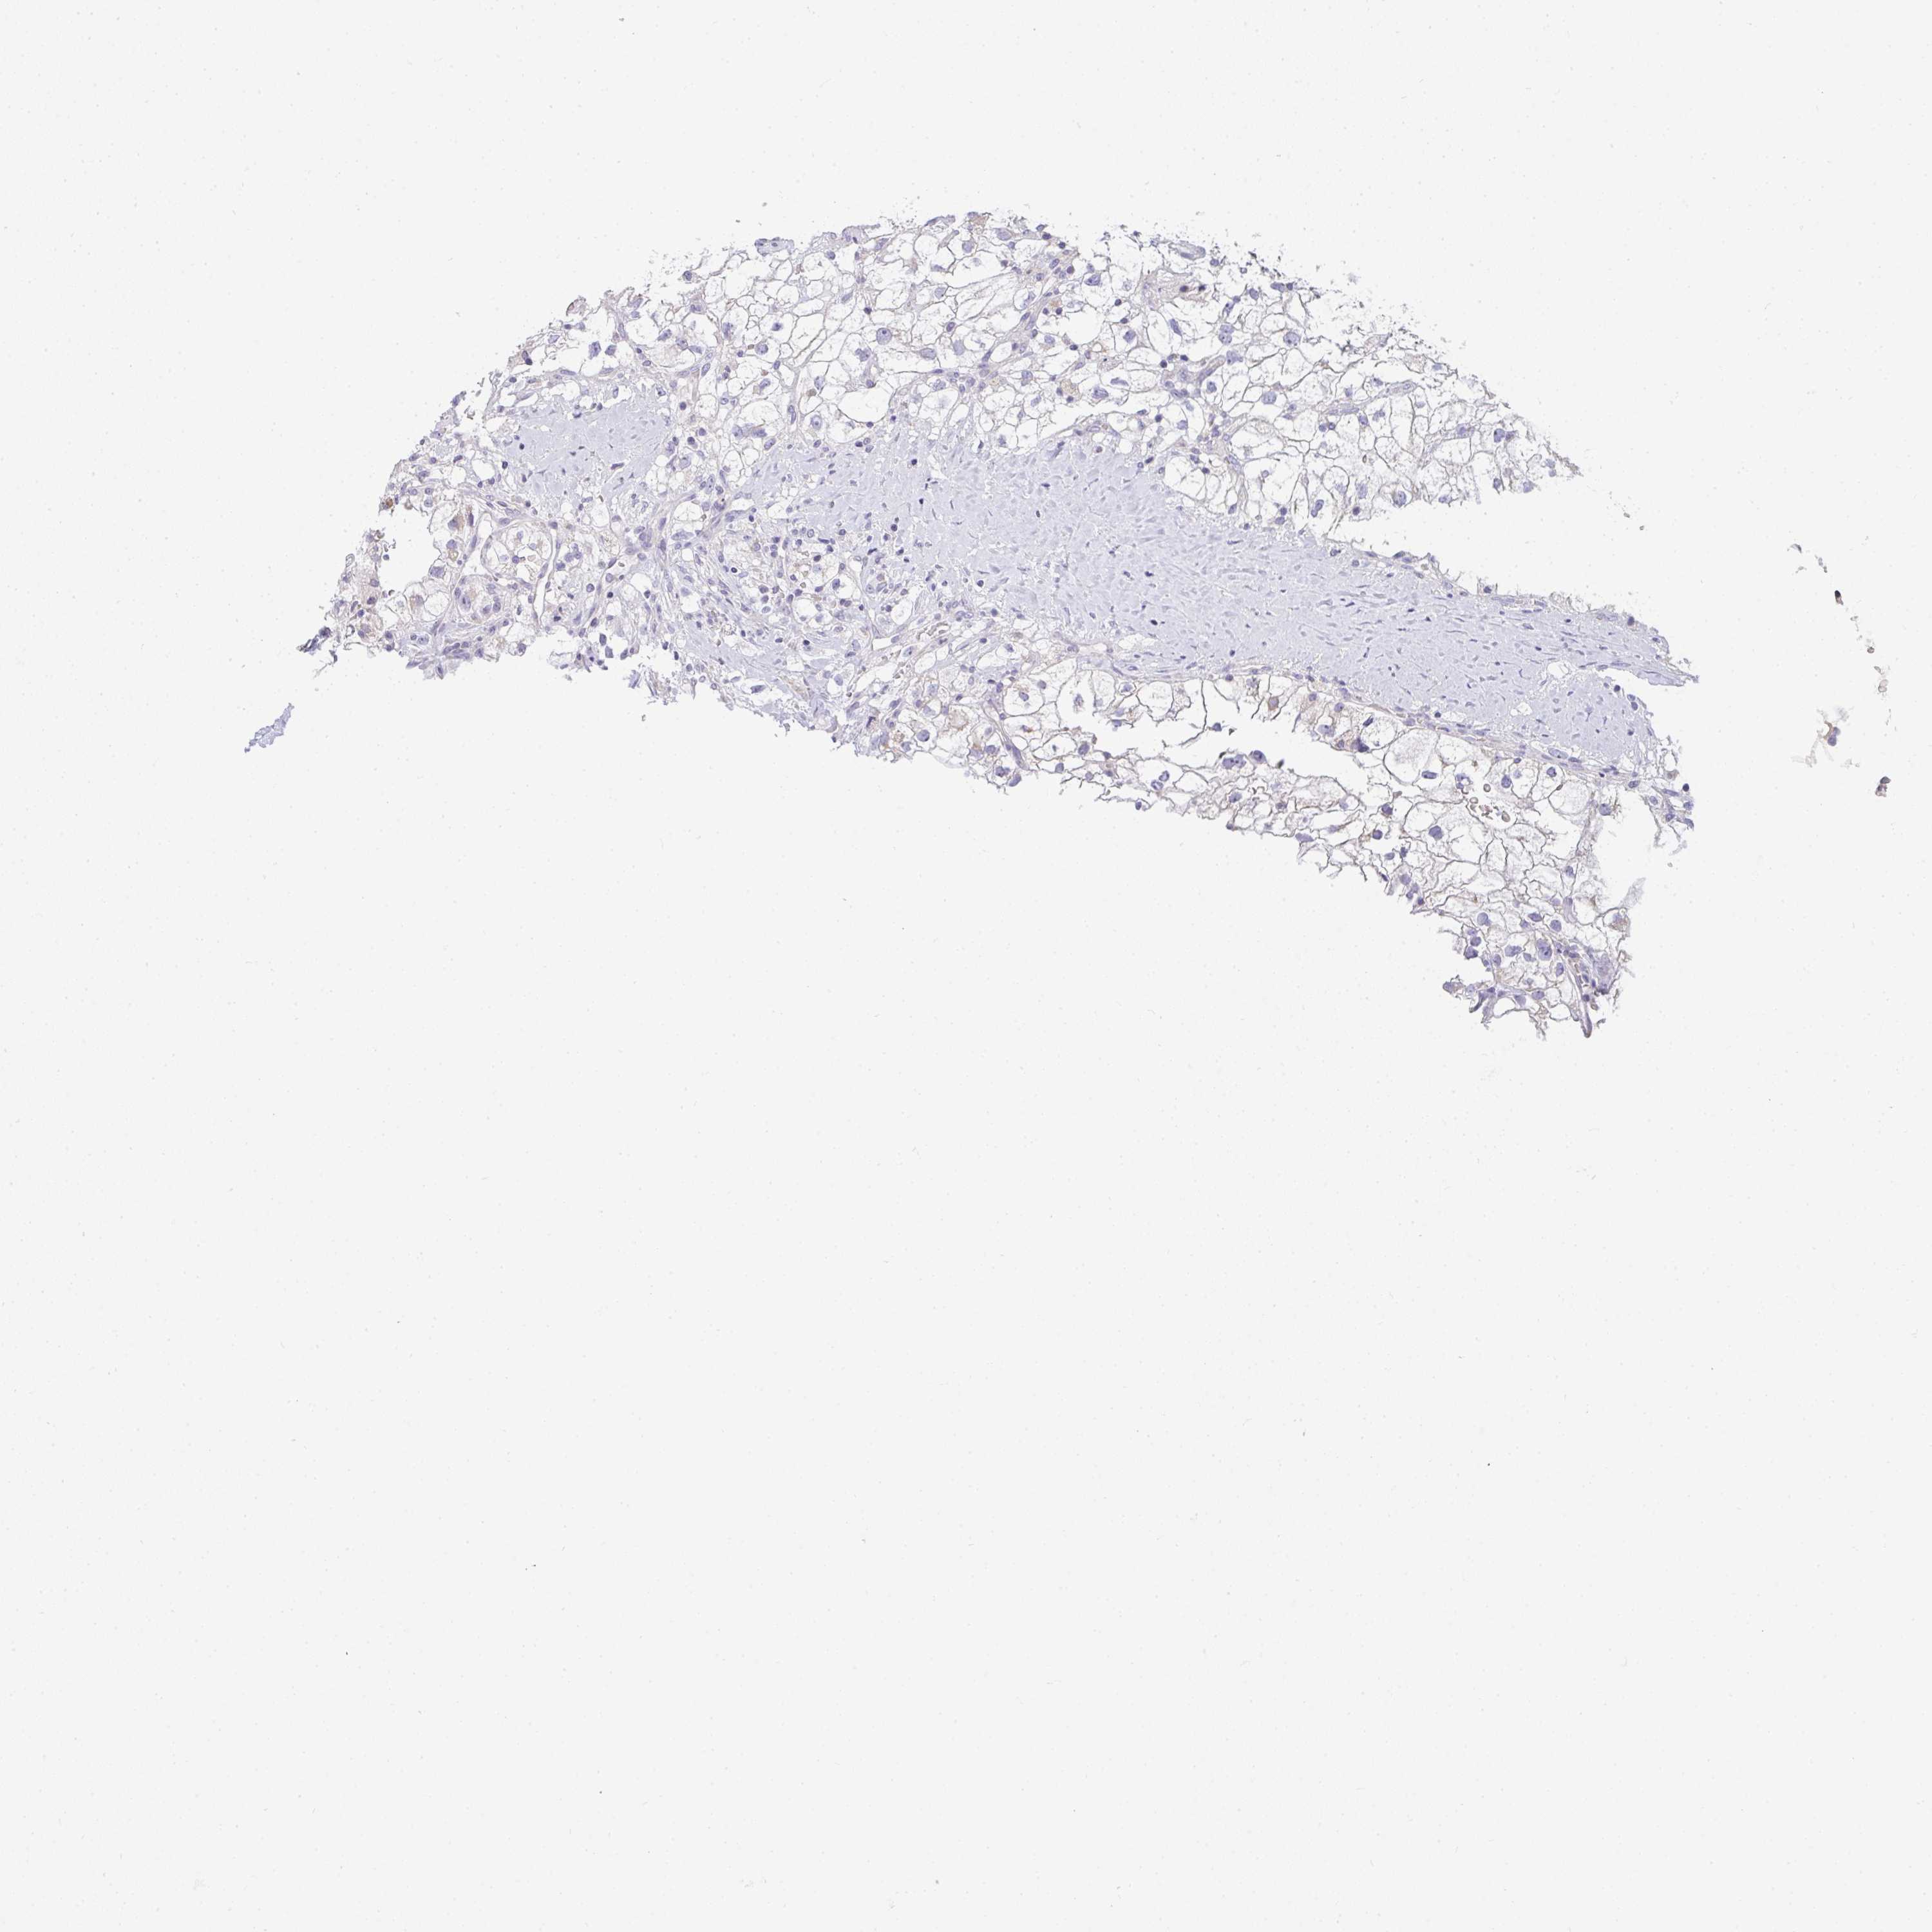

KIDNEY RENAL CLEAR CELL CARCINOMA (VALIDATION) - Interactive survival scatter ploti

The Survival Scatter plot shows the clinical status (i.e. dead or alive) for all individuals in the patient cohort, based on the same data that underlies the corresponding Kaplan-Meier plots. Patients that are alive at last time for follow-up are shown in blue and patients who have died during the study are shown in red.

The x-axis shows the expression levels (FPKM) of the investigated gene in the tumor tissue at the time of diagnosis. The y-axis shows the follow-up time after diagnosis (years). Both axes are complimented with kernel density curves demonstrating the data density over the axes. The top density plot shows the expression levels (FPKM) distribution among dead (red) and alive patients (blue). The right density plot shows the data density of the survived years of dead patients with high and low expression levels respectively, stratified using the cutoff indicated by the vertical dashed line through the Survival Scatter plot. This cutoff is automatically defined based on the FPKM cutoff that minimizes the p-score. The cutoff can be changed by dragging the vertical line or by entering a cutoff value in the square labeled "Current cut-off".

Under the Survival Scatter plot the p-score landscape (black curve; left axis) is shown together with dead median separation (red curve; right axis). Dead median separation is the difference in median mRNA expression between patients who have died with high and low expression, respectively. It is calculated as follows: median FPKM expression of dead patients with high expression - median FPKM expression of dead patients with low expression. This is intended to aid the user in visually exploring custom cutoffs and the associated p-scores and dead median separation.

Individual patient data is displayed and can be filtered by clicking on one or more of the category buttons on the top of the page. Categories describing expression level and patient information include: high, low, alive, dead, female, male and tumor stages. The scale of the x-axis can be toggled between linear and log-scale by clicking on the "x log" button. Mouse-over function shows TCGA ID, patient information and mRNA expression (FPKM) for each patient.

& Survival analysisi

Kaplan-Meier plots summarize results from analysis of correlation between mRNA expression level and patient survival. Patients were divided based on level of expression into one of the two groups "low" (under cut off) or "high" (over cut off). X-axis shows time for survival (years) and y-axis shows the probability of survival, where 1.0 corresponds to 100 percent.

GSDMB is not prognostic in Kidney Renal Clear Cell Carcinoma (validation)

: 3.94

Average pTPM 3.8

Number of samples 100